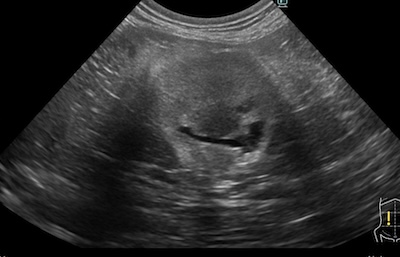

術前、術後のエコー比較

腎瘻チューブ抜去後、尿路の疎通が問題がないことを確認して退院としました。